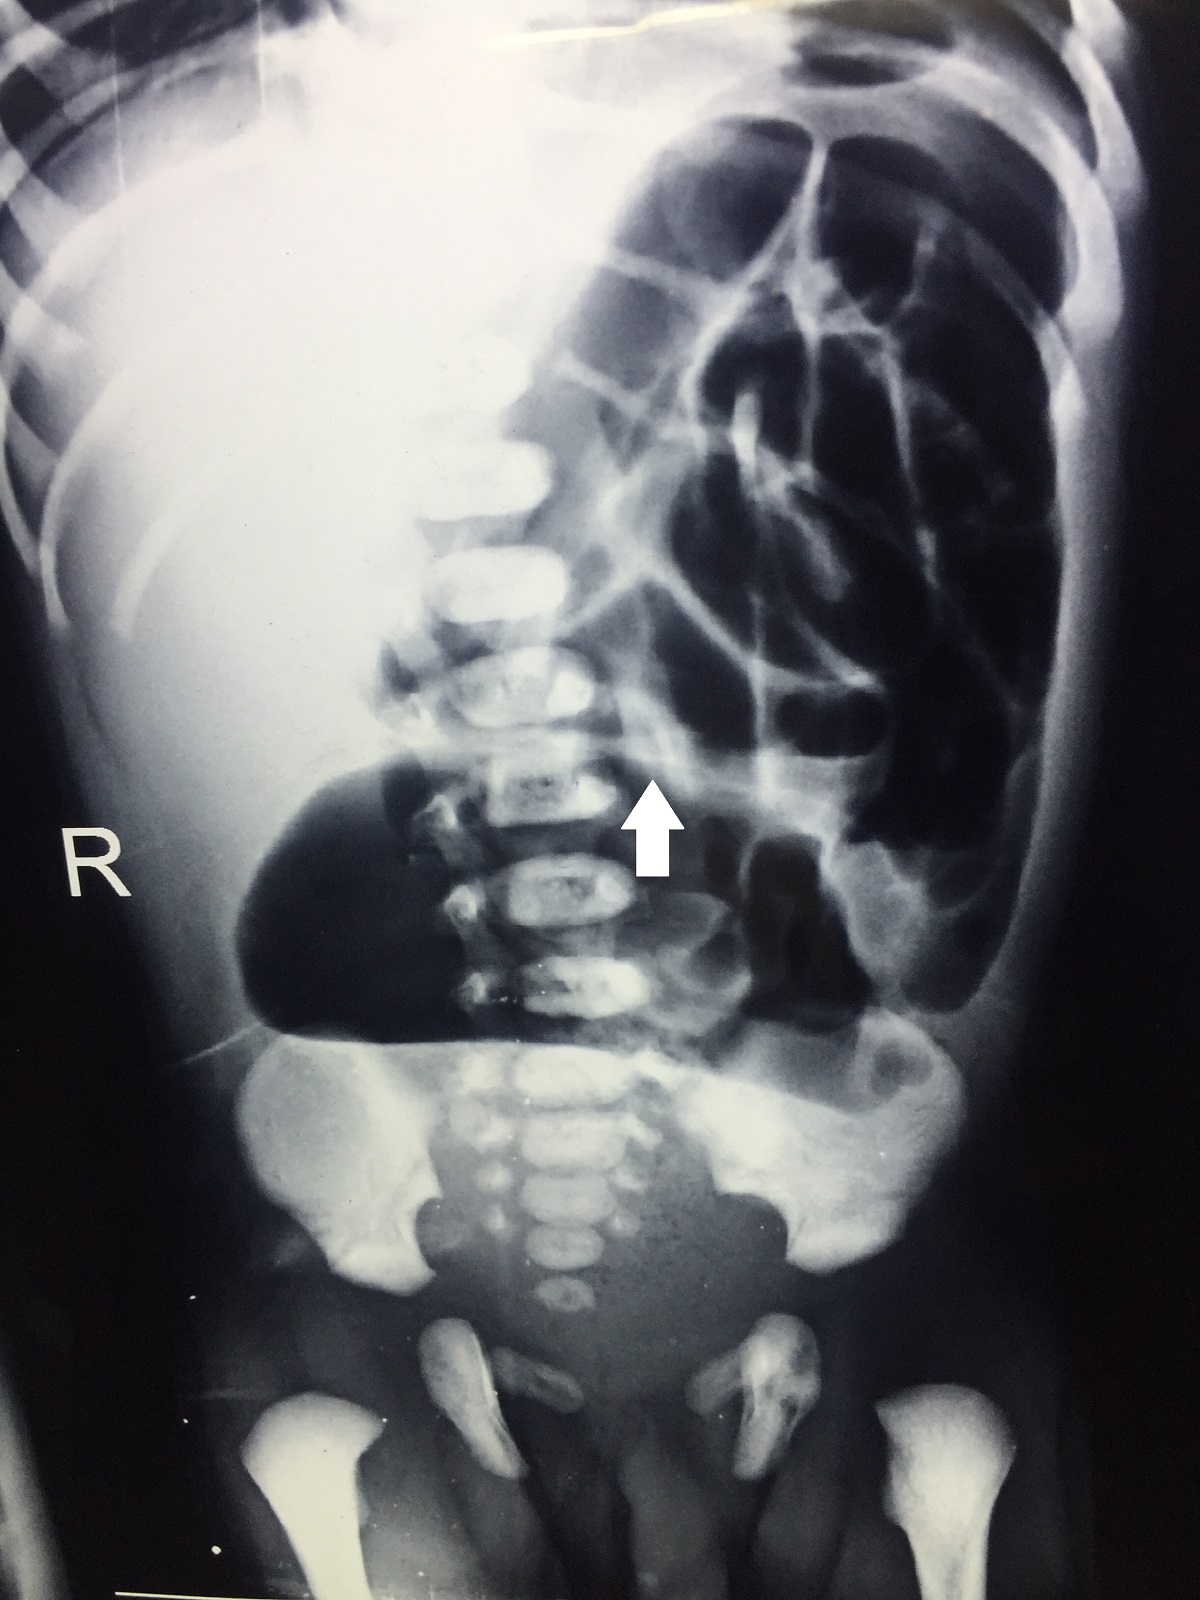

Routine investigations, namely complete blood counts, renal and liver function tests were within normal limits, and the septic screen was negative. The abdominal radiograph showed dilated colonic shadow, occupying more than half of the abdomen, suggestive of CPC type 2 as the apex of the pouch was directed towards the left hypochondrium (Fig. 1).[3] Abdominal ultrasonography was suggestive of left hydroureteronephrosis; with normal right kidney. 2D echocardiogram was normal.

Figure 1

Plain abdominal radiograph showing dilated pouch with the apex directed towards left hypochondrium (marked with white arrow).